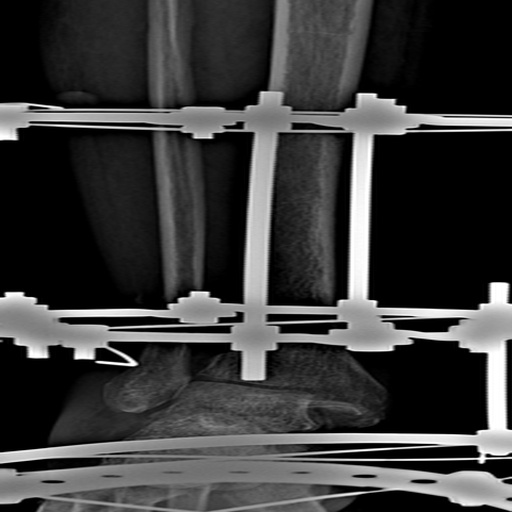

It identifies hairline fractures in medical imaging

We preprocessed the data, then trained and validated the model, then tested the model